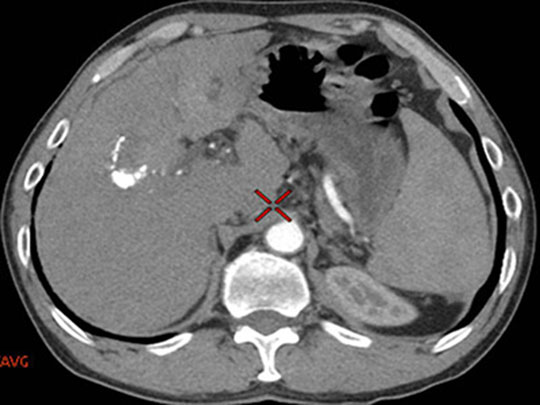

病例点评及临床价值: 常规CT增强扫描,病灶有无强化直接影响病变的定性诊断,然而血肿、钙化在CT图像上亦呈高密度影,难以辨别,往往需要多期扫描,甚至追加平扫来加以鉴别、区分,增加患者辐射剂量。

能谱CT扫描能够获得各种基物质图像,在一期扫描中对病灶强化、血肿、钙化加以区分,满足病变定性需求,同时降低患者辐射剂量。

利用Water/Iodine基物质图像区分增强和血肿 利用Calcium./Iodine基物质图像区分钙化和增强 利用Water/Calcium基物质图像区分钙化和血肿